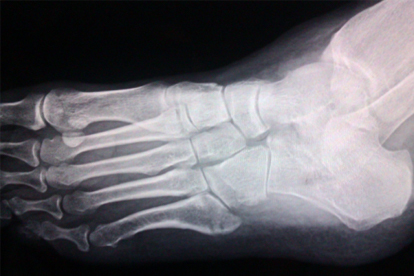

脚骨折后应保证每日摄入足够的优质蛋白如鱼肉、鸡蛋,补充富含维生素D的食物如深海鱼、蛋黄。适当增加奶制品、豆制品等钙质来源,配合适度的阳光照射促进钙吸收。恢复期间避免吸烟,保持规律作息,根据医生建议进行循序渐进的康复训练。定期复查X线观察骨折愈合情况,如出现异常肿胀、疼痛加剧等情况需及时就医。